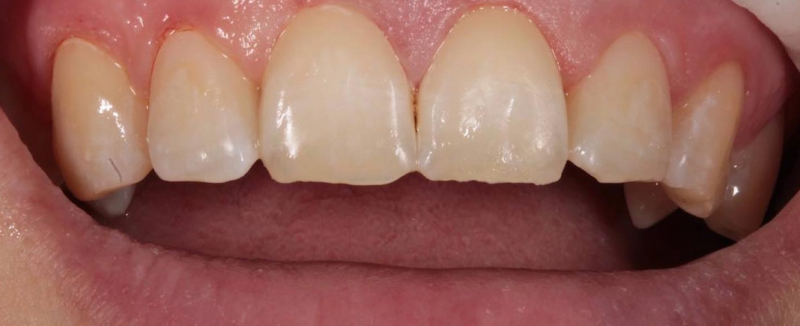

На странице представлено портфолио стоматологий Санкт-Петербурга с работами до и после профессиональной чистки зубов. В нашем портфолио собраны разные клинические случаи: от удаления незначительного налета до снятия массивного поддесневого камня. Здесь вы можете увидеть, как возвращается естественный цвет и внешний вид зубов после процедуры. Изучите результаты до и после чистки зубов, чтобы увидеть реальный эффект и выбрать клинику в Санкт-Петербурге, где профессиональная гигиена поможет вернуть зубам здоровый вид.